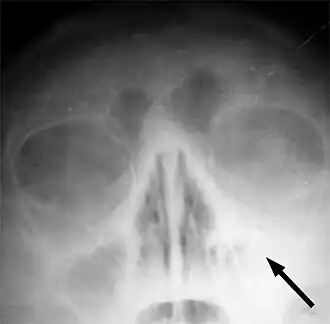

Le sinus maxillaire gauche marqué d'une flèche. On note l'absence de transparence aérique par rapport au côté opposé.

Une radiographie n'est utile qu'en cas de doute sur le diagnostic ou éventuellement après un premier échec de traitement par antibiotiques. Le scanner n'est quant à lui indiqué qu'en cas de suspicion de sinusite complexe ou sphénoïdale, cette dernière n'étant pas visible par radiographie.